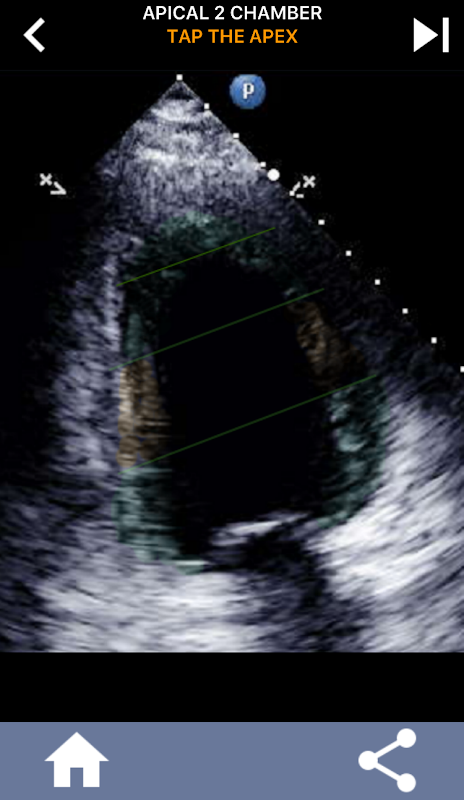

초음파 심장 초음파 검사는 좌심실의 미국 심장 협회 심장 세분화를 자기 공명 영상, 심장 핵 검사 등과 같은 다른 많은 영상 진단법에서 널리 사용되는 표준 인 17 개 세그먼트로 학습하는 것이 필수적입니다. 영향을받는 세그먼트 및 기능의. 여러 번 에코를 읽는 사람이 "무엇을 보았습니까?"라고 묻습니다. 영향을받은 지역의 정확한 위치로 회신하는 것이 예상됩니다.

이 응용 프로그램은 AHA로 구분 된 심근을 보여주는 모든 반향보기를 포함하고 올바른 부분을 탭하도록 퀴즈 것입니다. 나는 개인적으로 빨리 반복적 인 퀴즈가 나를 위해 가장 잘 작동한다는 것을 알았다. 나는 주제를 빨리 배우고 암기해야한다. 당신이 에코 / TTE를 공부하는 초음파 학생이라면, 이것은 당신의 연구에 훌륭한 보완책이 될 것이라고 생각합니다.